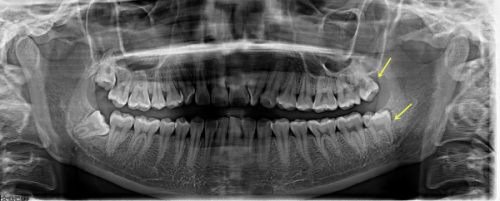

再者,医院采用的数字化种植技术误差率 < 0.1mm,可避免神经血管损伤。在进行单颗瑞士ITI种植牙手术时,精细的操作至关重要。数字化种植技术能够让医生更正确地规划种植位置和角度,确保种植体的稳定性和安心性,为患者带来更好的种植成效。

在技术靠谱方面,院长王林为原杭州口腔医院种植科骨干医生,团队90%有国有履历,医生资质实力强。医院还配备了意大利NewTom CT、瑞士士卓曼种植机,精度对标省级,精良的设备为种植牙手术提供了有力的支持。并且,医院遵循ISO种植手术标准化流程,术后48小时电话随访,严格的质控体系确保了手术的质量和患者的安心。